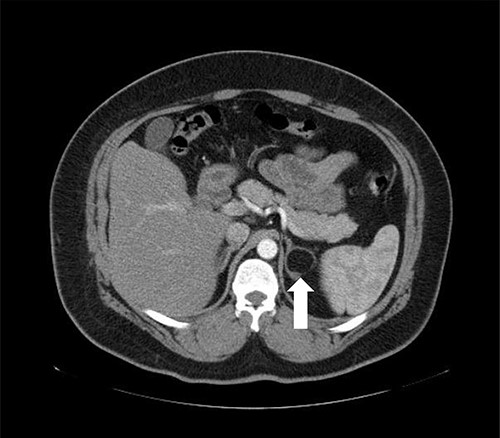

A 37-year-old male, with a BMI of 42 kg/m2, dyslipidemia HTN and gout, presented to our private clinic with progressive weight gain. He also reported an incidental 1.6 cm left adrenal mass on a CECT of the abdomen, which was done in 2014. A repeated CECT showed a larger left adrenal mass of 5 cm, which was lobulated and suggestive of atypical lipid-poor adenoma (Fig. 3). A biochemical workup showed normal serum metanephrine of 50 ng/l (reference <90), normal serum normetanephrines of 90 ng/l (reference <129) and serum morning cortisol of 250 nmol/l. Considering the increasing size of the left adrenal gland and the patient's concerns about it, a LSG combined with LLA was offered to the patient for weight management and diagnosis confirmation of the left adrenal gland.

Axial CT of the abdomen showing the left adrenal mass in Patient 3 (white arrow).